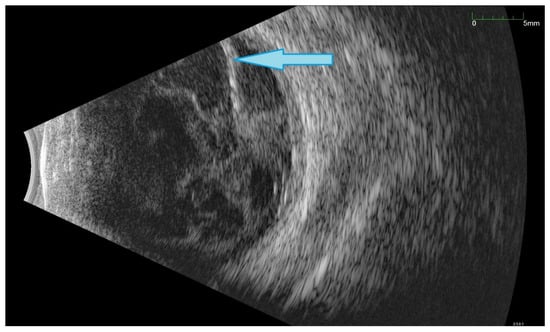

All of the above circumstances make the assessment of the vitreous body and retina in an ophthalmoscopic examination often impossible. The basic diagnostic tool in such cases is an ultrasound examination. Vitritis is inherent part of EE. Ultrasonography is nonspecific, however, it can indicate severity of the posterior involvement (Figure 6 and Figure 7) [80]. It also allows the assessment of the progression of changes (Figure 8). Features characteristic for EE include strands and membranes with reduced mobility (Figure 9). Other common changes are retinal detachment and subretinal abscess (Figure 10).

Figure 8.

Ultrasound B scans showing the evolution of changes during the development of inflammation. (A,B)—vitritis, posterior vitreous detachment (blue arrow), and retinal thickening. (C,D)—retinal detachment (green arrow) and numerous hyperechoic densities in the vitreous chamber (blue arrowhead).

Figure 9.

Ultrasound examination showed hyperechoic densities and point tractions on the retina (blue arrowhead). Densities forms strands and membranes with reduced mobility (green arrowhead). In order to confirm that the retina is not detached, the A-scan was superimposed over B-scan.

Figure 10.

Ultrasound B scan with numerous hyperechoic densities in vitreous chamber. The blue arrow marks a detached retina. Hyperechoic masses are visible under the retina.